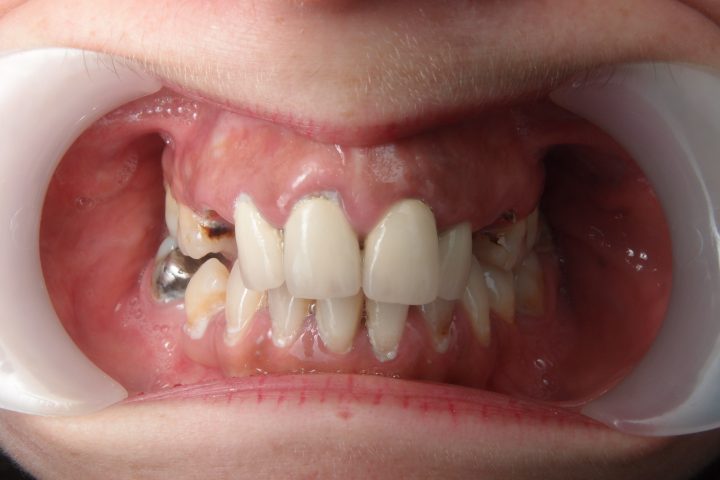

Clive kam aus England, und war im Jahr 2016 bei uns. Früher war er Berufsboxer, deswegen hatte er abgehärmte Zähne. Bis seinem 50. Geburtstag hat er sehr viele Zähne verloren, und die übrigen waren abgebrochen und verfärbt.

Er hatte 10 Tage lange Behandlung in der Zahnklinik Centrocc Dental. Sein Traum wurde erfüllt, Frau Dr. Erdélyi hat ihm schneeweißes, ausgezeichnetes Lächeln mit der Hilfe von 18 Stück Metallkeramik Kronen gezaubert.